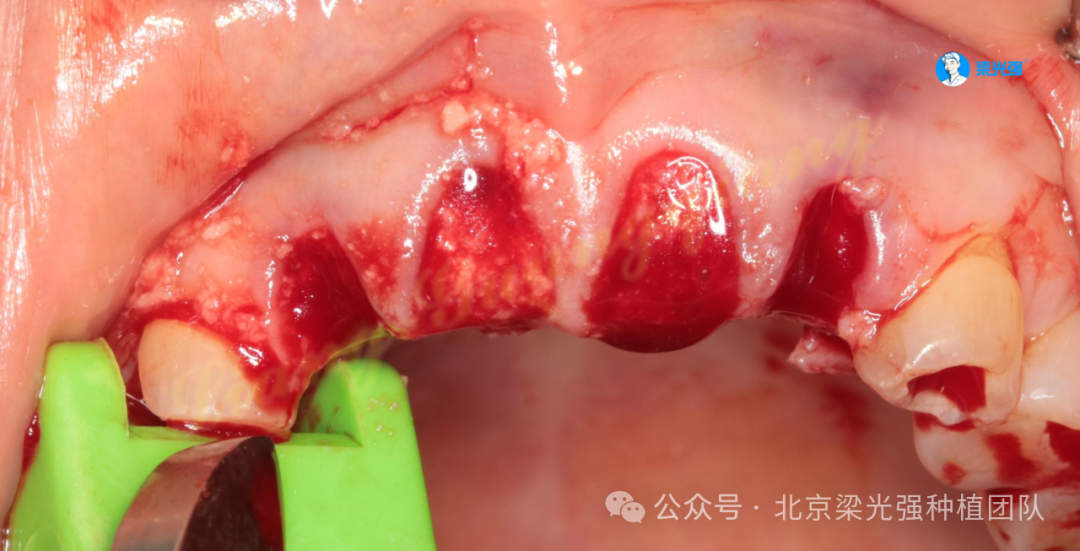

12-22局麻下拔除,先锋钻备洞,用平行杆观测方向,植体植入三要素:位点、方向、深度。首先确定的是位点和方向。

将保留下来的自体骨柱研磨成自体骨屑:由于骨密度为四类骨,密度太小,植入植体前先将骨屑塞入窝洞,以便增加摩擦力。

21未植入植体,拔牙窝放了吸收慢的小牛骨,可以长时间维持牙槽骨的丰满度,防止塌陷:

交叉缝合锁住胶原蛋白:

牙槽嵴顶用金刚砂车针去除上皮层。

安装愈合基台将去上皮的角化龈折叠翻转推到唇侧,以增加唇侧附着龈厚度。